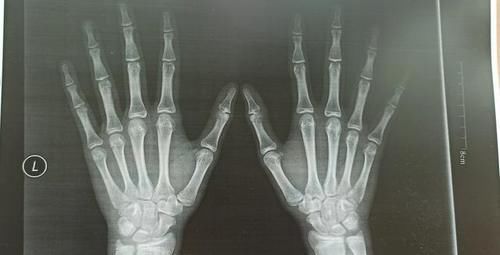

现在我家孩子15岁半了,身高只有167cm,体重49公斤。感觉好几个月都没怎么长高。去医院拍了骨龄照,结果不是很理想。

这种情况应该没有什么长高的空间了。有点后悔当初自行停药,应该给孩子再接着打生长激素的。但是没有后悔药吃。